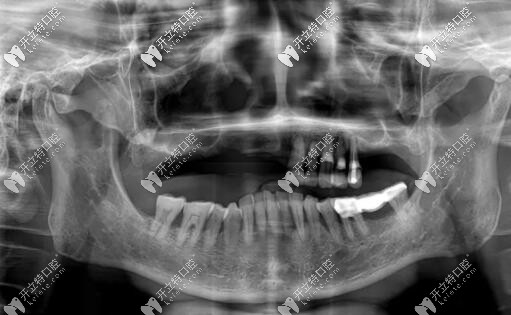

惠先生種植方案:前期ALL-ON-4即刻負(fù)重,后期上頜竇外提升,同期植入兩顆種植體,做ALL-ON-6,馬龍一體橋。

西安美奧口腔種植牙案例

目前已完成ALL-ON-4即刻負(fù)重,通過手術(shù)情況來(lái)看,效果確實(shí)比較好,作為一位地道老陜?nèi)?,惠先生的感激之情溢于言表?/p>